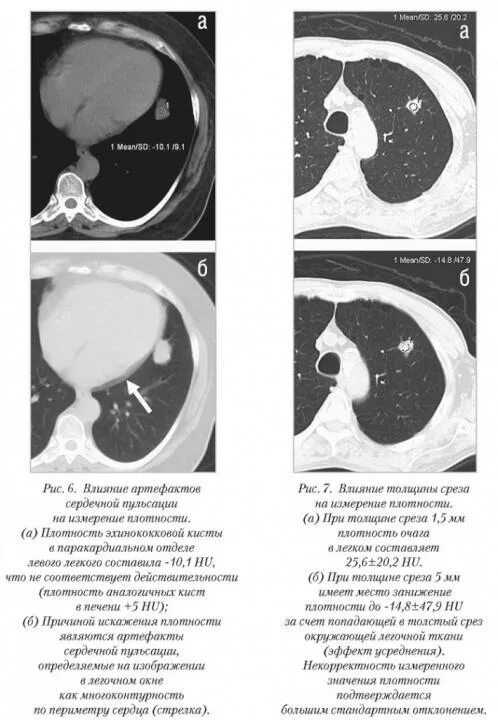

Плотность на кт